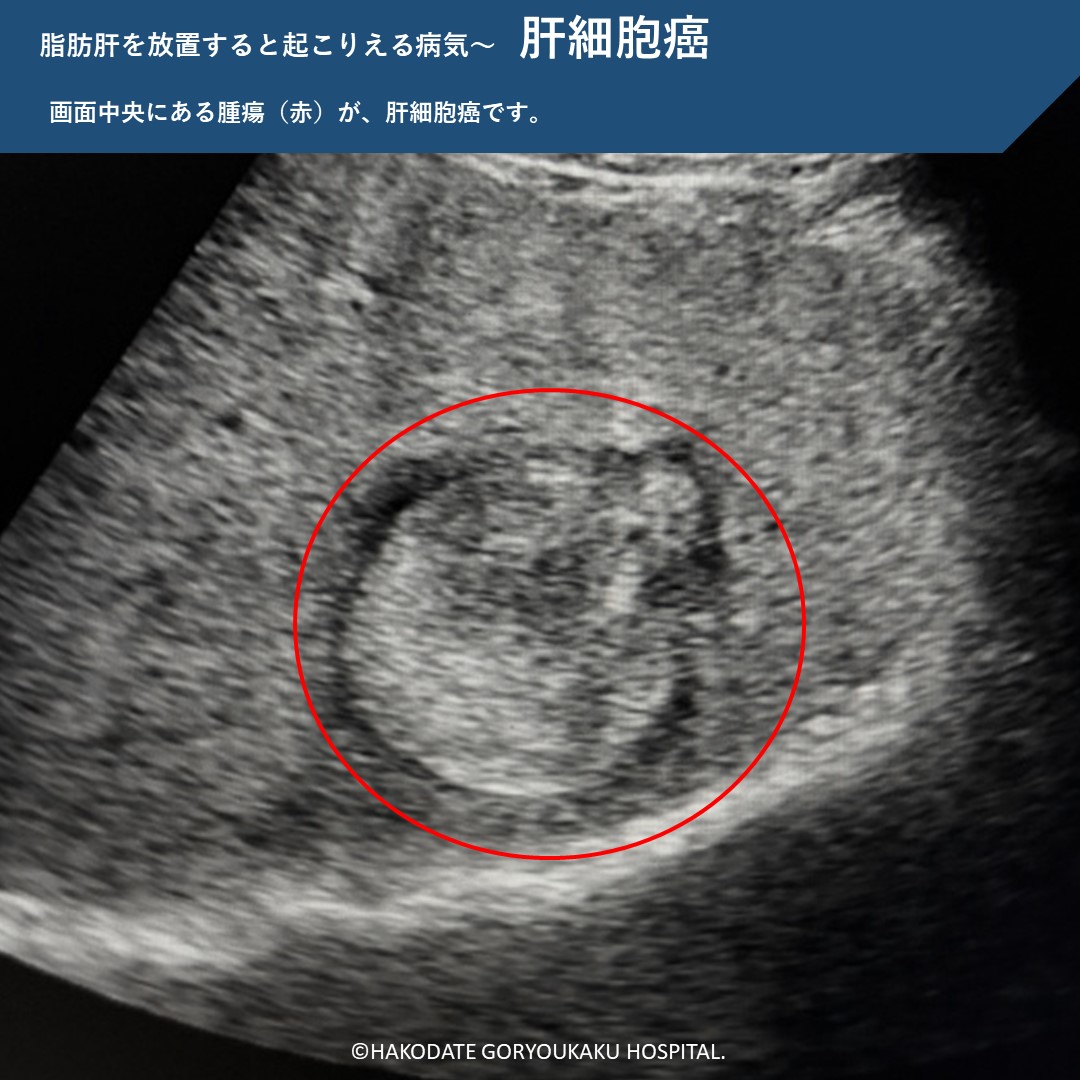

脂肪肝を放置すると

脂肪肝を放置すると、肝臓に炎症が起こり、やがて肝硬変に移行します。肝硬変になると肝細胞癌のリスクが上がります。また、こういった肝臓の病気だけでなく、心筋梗塞や脳卒中、肝臓以外の悪性腫瘍の原因にもなります。特に「メタボ+飲酒+脂肪肝」の組み合わせは、肝臓に関連する病気の死亡率や、肝細胞癌の発生リスクが高い事がわかっています。